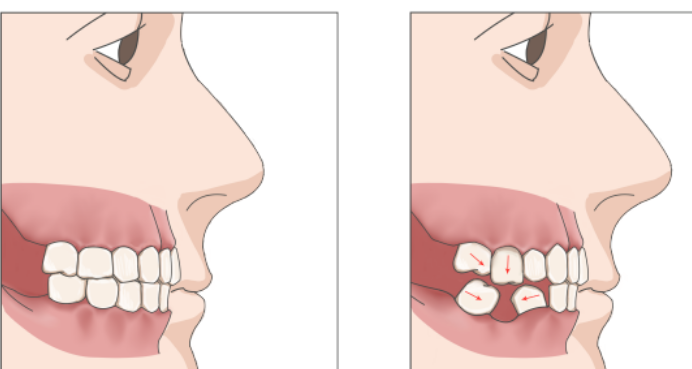

长期缺牙会使邻牙向空缺处倾斜,对颌牙伸长,导致相邻牙齿间的缝隙逐渐扩大。